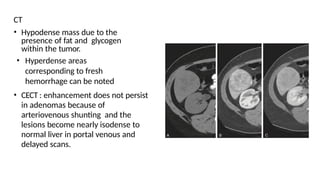

CT

• Hypodense mass due to the

presence of fat and glycogen

within the tumor.

• Hyperdense areas

corresponding to fresh

hemorrhage can be noted

• CECT : enhancement does not persist

in adenomas because of

arteriovenous shunting and the

lesions become nearly isodense to

normal liver in portal venous and

delayed scans.